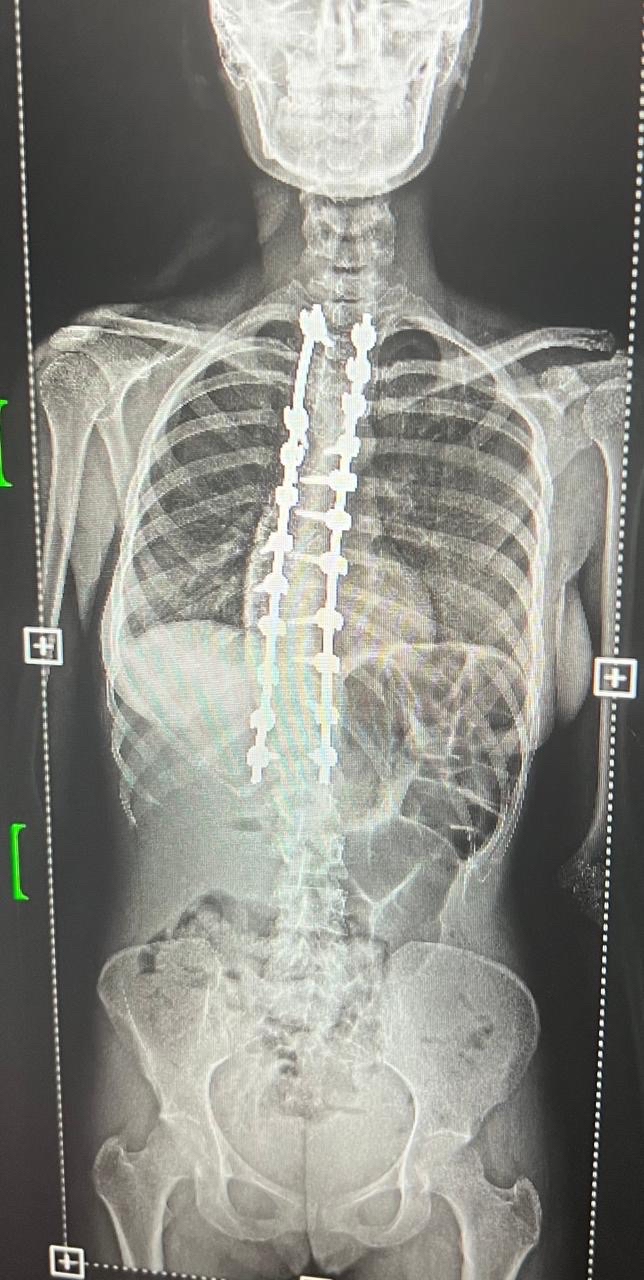

وخضعت الحالتان لتقييم طبي شامل ودقيق تضمن إجراء كافة الفحوصات الإكلينيكية والأشعة المتخصصة، التي كشفت عن وجود تشوهات ودرجات انحناء متقدمة استوجبت التدخل الجراحي العاجل لتفادي المضاعفات.

واستعان الفريق الطبي بأحدث التقنيات العالمية في هذا المجال، معتمداً بشكل أساسي على أجهزة المراقبة العصبية الدقيقة لضمان أعلى معايير الأمان وسلامة الأعصاب الحساسة أثناء إجراء التعديل.